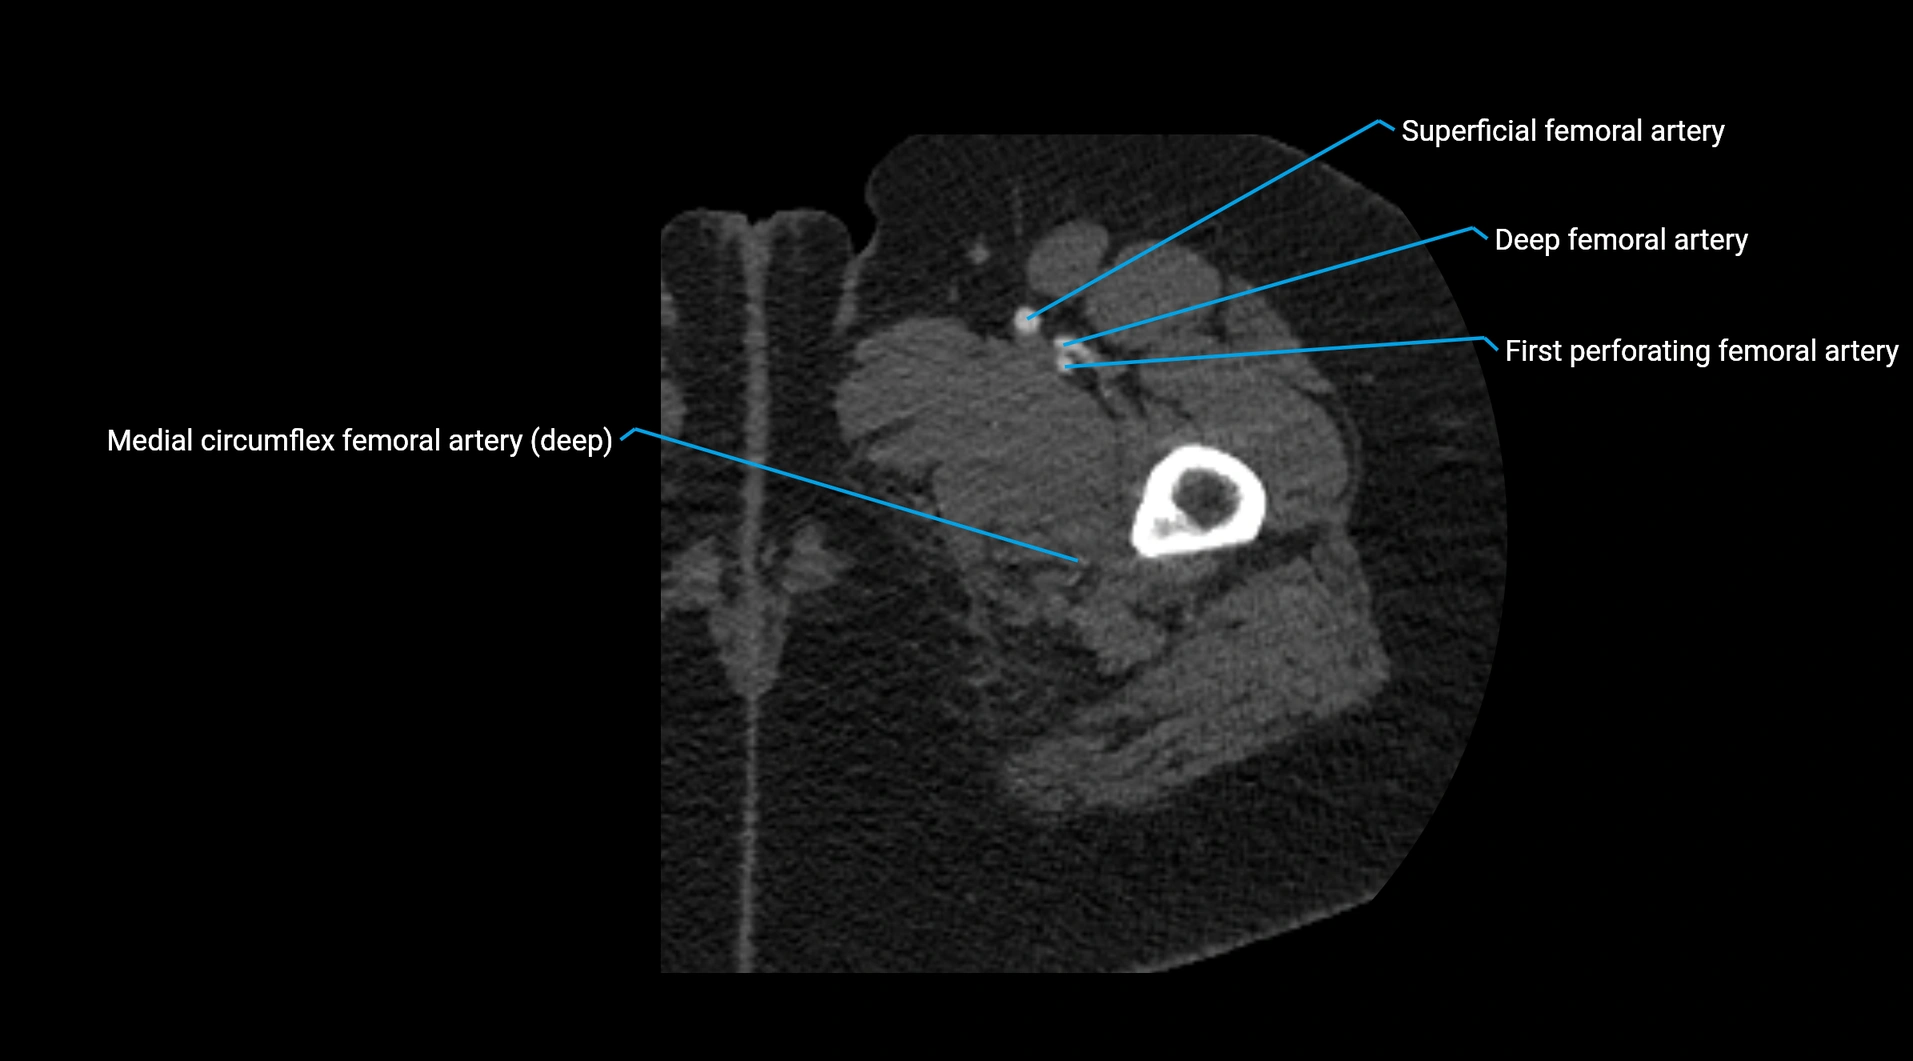

CT images

image